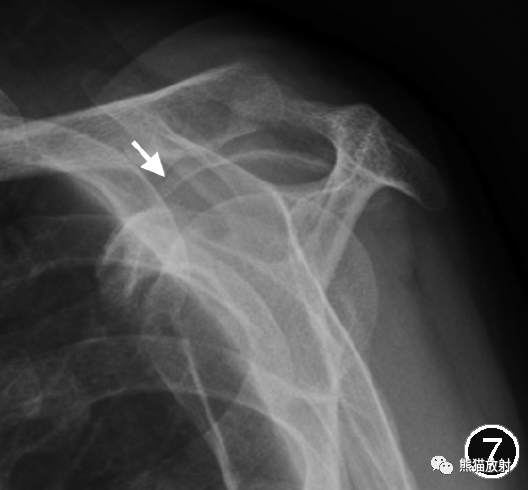

图1 X线片评估肩峰形态。冈上肌出口位X线片示肩峰前部呈钩形(↑),为Ⅲ型肩峰。

图7 肩峰骨刺的X线片。冈上肌出口位示肩峰前下缘喙肩韧带附着处骨刺(↑)